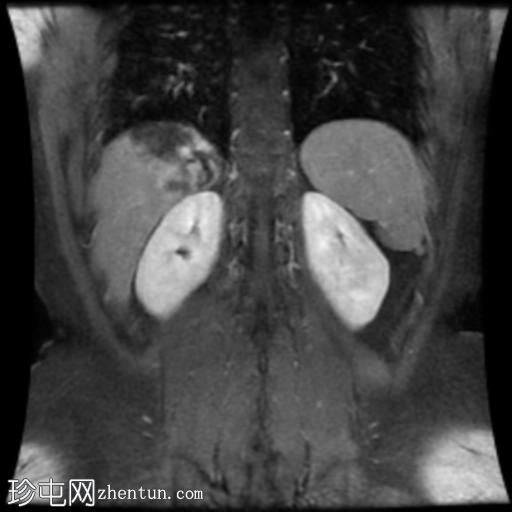

冠状位T1加权像增强扫描

轴位T1加权像增强扫描

10.jpg

肝脏第7段可见一边界清晰的分叶状肿块。T1加权像呈低信号,T2/T2脂肪抑制序列呈高信号,动脉期呈不连续结节状周边强化,门静脉期呈向心性强化,延迟期完全强化。DWI序列呈高信号,ADC值呈混合信号。